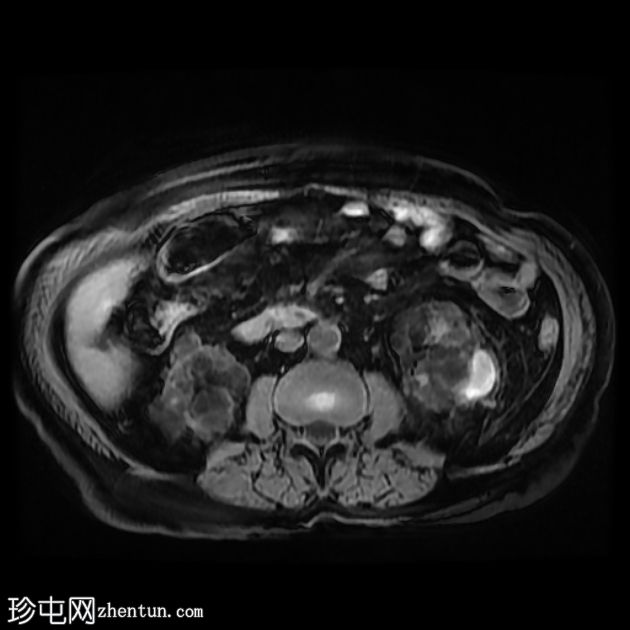

轴位

T2加权像

双侧肾囊性疾病,可见多个肾囊肿,其中许多呈复杂性(出血性)囊肿,T1加权像呈高信号,T2加权像呈低信号。

左侧可见一较大的肾周血肿,与上极出血性囊肿相连,提示出血性囊肿破裂(Wunderlich综合征)。

未见肾脏软组织肿块。

轻度肝脾肿大,受检骨骼T2加权像呈弥漫性低信号,提示肾性骨营养不良。